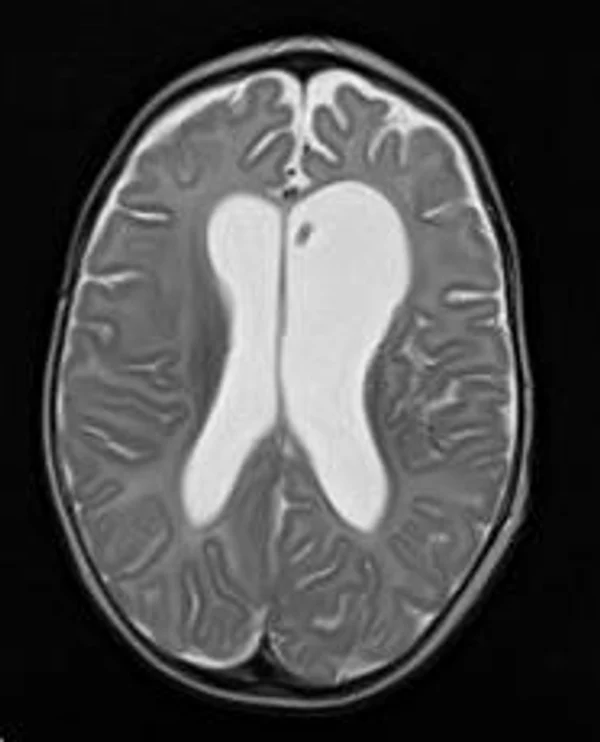

Гидроцефалия

Основной причиной гидроцефалии является окклюзия ликворных путей, встречающаяся у новорожденных детей в 60-70% случаев, к 3 годам частота окклюзионной гидроцефалии достигает 90%. Поэтому основной задачей лечения гидроцефалии являются устранение окклюзии ликворных путей, восстановление циркуляции ликвора и нормализация внутричерепного давления. В настоящее время эти задачи успешно позволяют решить эндоскопические методы хирургического лечения гидроцефалии. Эндоскопические операции проводятся нами во всех возрастных группах, включая недоношенных новорожденных детей, при разных локализациях и количествах окклюзий. При этом если эндоскопическая перфорация дна III желудочка (син.: эндоскопическая III-вентрикулостомия) малоэффективна у детей до 2-3-х летнего возраста, то новые методы эндоскопических операций, направленные на реканализацию естественных путей оттока ликвора с имплантацией стента (например эндоскопическая акведуктопластика, стентирование водопровода мозга) позволяют избежать имплантации шунтирующих систем у большинства пациентов с окклюзионными формами гидроцефалии. С целью снижение объема секреции ликвора и увеличения эффективности эндоскопических опеарций в некоторых случаях в комплексе с другими эндоскопическими операциями проводится эндоскопическая плексусэктомия. Операция заключается в коагуляции сосудистых сплетений боковых желудочков с последующим удалением их гломусных частей. Эндоскопические операции также проводятся при дисфункции ранее установленных шунтирующих систем у пациентов с окклюзионной гидроцефалией, что часто избавляет пациента от «шунт зависимости» и создает условия для удаления шунта. Имплантация ветрикулоперитонеальных, вентрикулоатриальных и др. шунтирующих систем нами применяется при сообщающейся форме гидроцефалии. У пациентов с окклюзионными формами гидроцефалии шунтирующие операции проводятся только при неэффективности ранее проведенных эндоскопических операций.